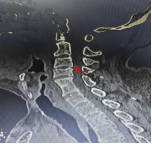

术前影像资料显示C3/C4椎间盘突出、极重度颈椎椎管狭窄、C5/6椎体融合

患者李某,70岁,因“四肢乏力、行走不稳1年,加重1个月”入住新利备用网骨科二区,入院检查诊断为:脊髓型颈椎病、颈椎椎管狭窄症(C3/C4极重度)、慢性不完全性四肢瘫。其中C3/4节段椎管占位率超过50%以上,脊髓受压极其严重,若病情继续进展,可能导致高位截瘫甚至呼吸衰竭,危及生命。且李某还存在C5、6节段先天性融合,短颈畸形,进一步增加了术中暴露和置钉的难度,对主刀医生的经验、技术及团队配合要求极高。